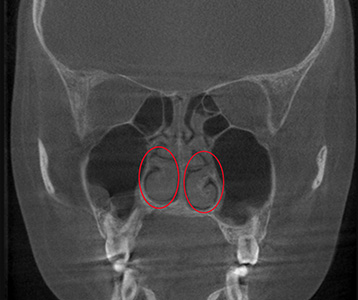

재수술 전